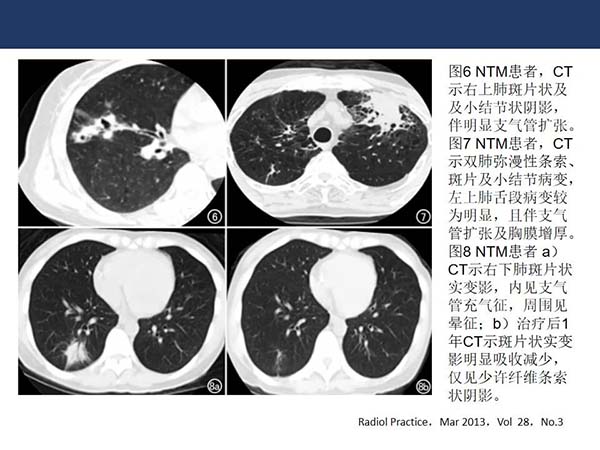

【杨柳病例】非结核分支杆菌肺病(NTMPD)